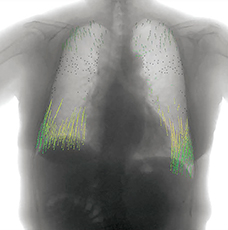

胸部単純X線写真では,下肺野優位に網状影,すりガラス状陰影が認められる。単純CT画像(図1)では,上肺野ほどの陰影はないが,下肺野には気管支血管側周囲から胸膜下にかけて網状影,すりガラス状陰影が認められ,膠原病肺が疑われる。胸部X線動態画像(図2)では,正常例と比べて下肺野および胸郭の幅の動きが悪い印象であった。また,胸部X線動態画像の呼気時から吸気時にかけての変位をベクトル表示した画像(図3)を見ると,当院の正常コントロール例と比較して下肺野の動きが悪い印象である。

図3 症例1:変位のベクトル表示画像